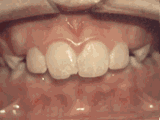

第八种

前牙反合,俗称“地包天”,也就是咬牙时,下牙盖住上牙,正常情况应该是上牙盖住下牙,经过矫正后的牙齿可以变成这样的~